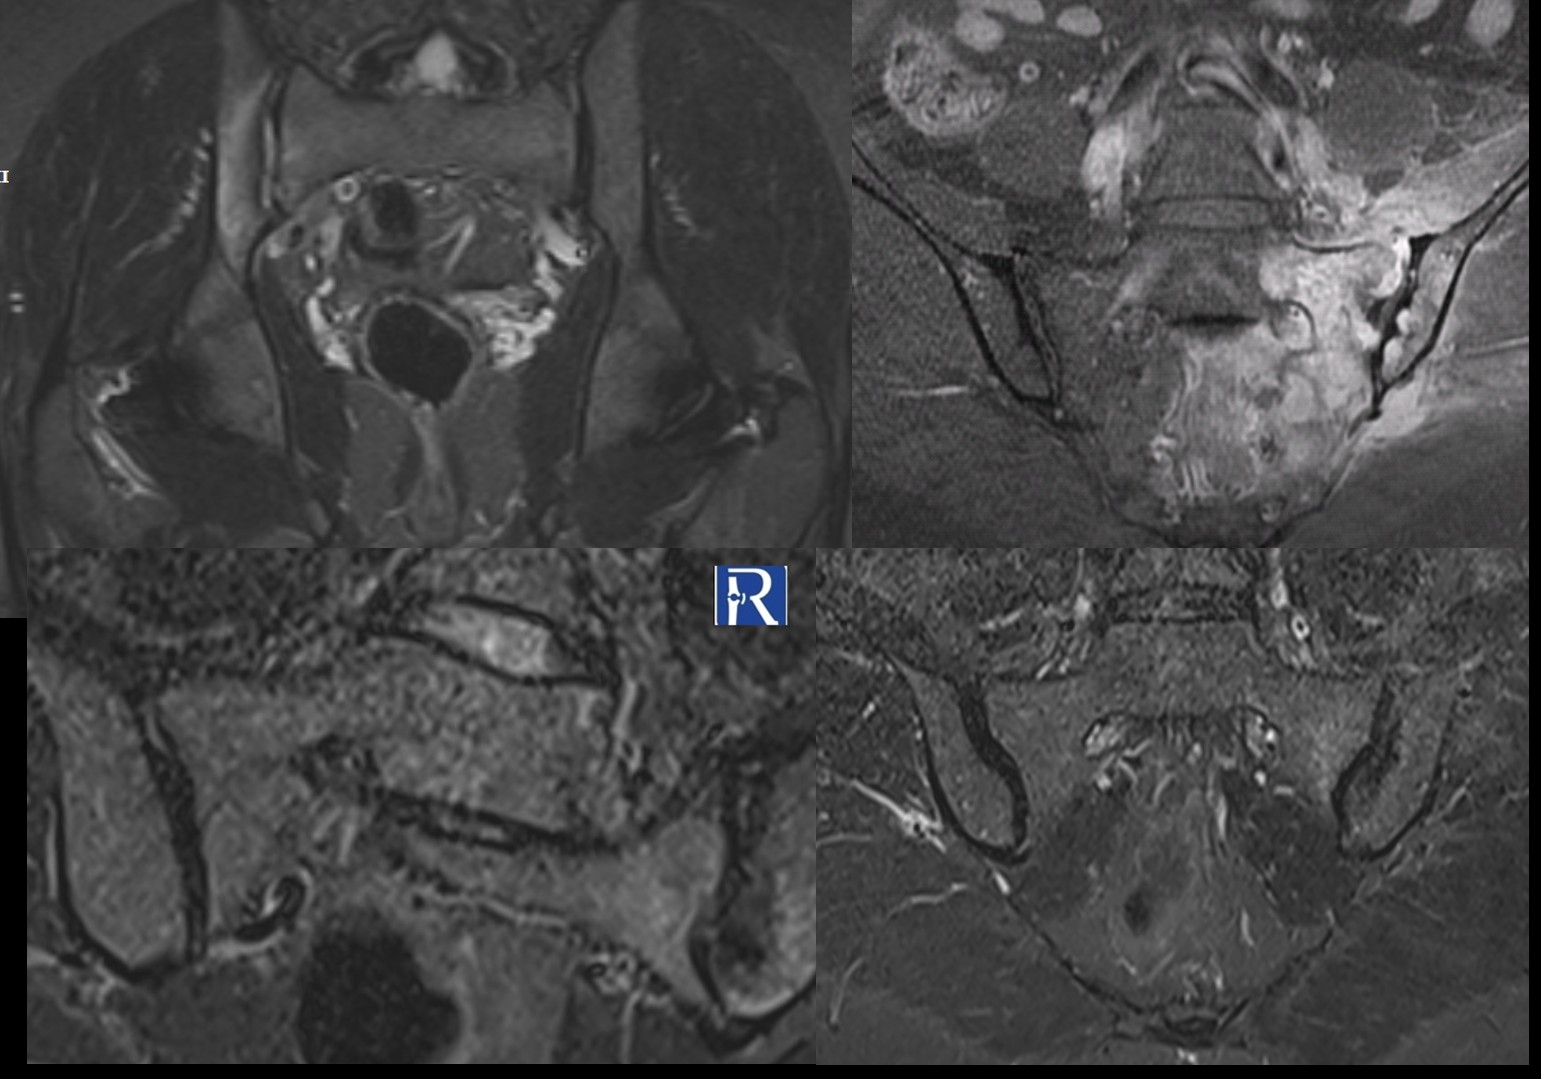

Case 1 Clinical presentation: A 36-year-old man presenting with right hip pain. The patient is HLA-B27 positive. MRI findings: MRI demonstrate ...